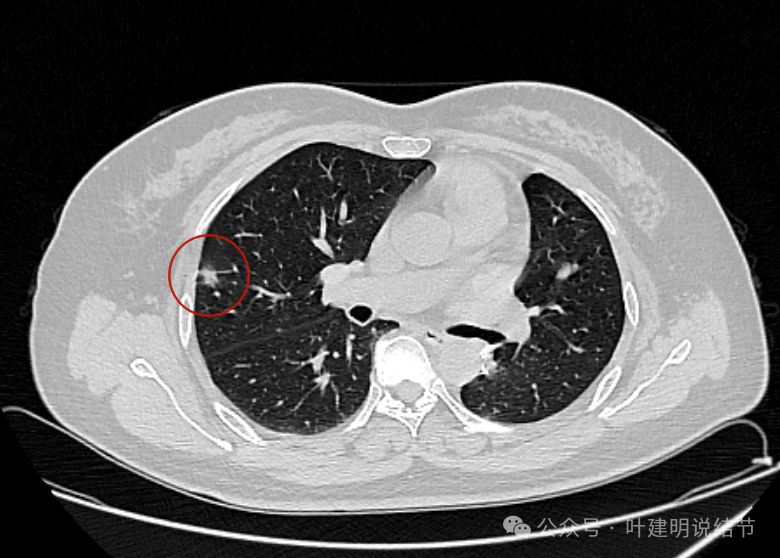

先看2024年5月时的片子:

病灶出现 ,边缘略显毛糙,有小血管进入,也见毛刺或小棘突征。